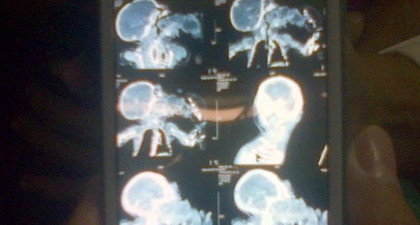

# kembar parasit

Kembar Parasit (2): Mengapa Bisa Terjadi?

Kembar Parasit (3): Bertahan Hidup dan Jadi Perhatian

Kembar Parasit (1): Ginan dan Kembaran Dalam Mulut